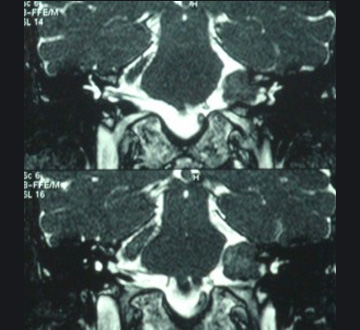

تومور در فضای بین مغز و گوش که زاویه پلی مخچه نامیده می شود، ایجاد می شود. آکوستیک نروما جزء تومورهای خوش خیم است اما خطر این تومور به دلیل رشد آن در فضای حساس و فشار آوردن آن به ساختارهای حیاتی مثل اعصاب جمجمه، مغز و ساقه مغز است. شایع ترین نشانه تومور شامل کاهش شنوائی در گوش مبتلا، وزوز گوش و عدم تعادل می باشد. برای بدست آوردن بهترین نتیجه، تشخیص صحیح به منظور انتخاب بهترین روش درمان در این اختلال ضروری است. برای تشخیص نورینوم آکوستیک انجام ام آر آی توصیه می شود. این روش تصویر برداری نه تنها به تشخیص کمک می کند بلکه وسعت و عوارض احتمال مانند هیدروسفالی را مشخص می کند.

نمونه های زیر MRI تعدادی از بیمارانی است که توسط دکتر اصغری جراحی شده اند: